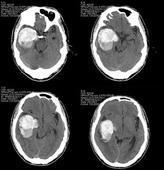

中樞神經系統結核瘤